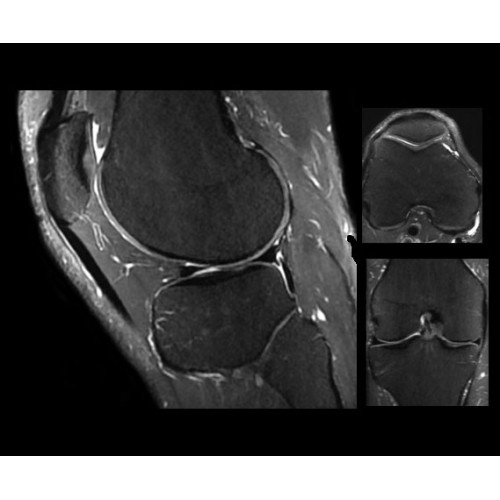

SIGNA PET/MR 3.0T — это гибридная система, в которой совмещаются две принципиально разные технологии — магнитно-резонансную томографию (МРТ) и позитронно-эмиссионную томографию (ПЭТ). Система отличающийся высокой чувствительностью и эффективностью и предназначена для диагностики в области онкологии, неврологии, кардио-васкулярных исследований, исследований воспалительных процессов.

Компания GE Healthcare представляет революционную, полностью интегрированную систему SIGNA PET/MR1, в которой сочетаются времяпролетная технология (TOF) и возможности напряженности магнитного поля 3.0 Тл. Мы поможем вам поднять исследования на более высокий уровень. SIGNA PET/MR позволяет достичь впечатляющей точности и скорости исследований, а благодаря новейшей технологии реконструкции Q.Clear2 качество изображений улучшается в два раза. Кроме того, в систему включен полный набор клинических приложений и гибких катушек для проведения любых видов исследования, открывая для вас возможности визуализации, о которых вы даже не догадывались.

Система SIGNA PET/MR предлагает впечатляющие клинические возможности и открывает доступ к наиболее полным пакетам программных приложений.